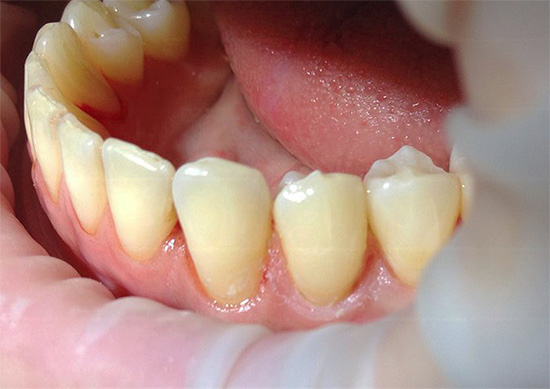

- Rimozione di depositi dentali sopra e sottogengivali: pulizia della placca e della pietra da tutte le superfici dei denti. Poiché la malattia gengivale è spesso innescata da tartaro e placca, al fine di effettuare una diagnosi corretta, è necessario pulire a fondo l'area di ispezione dai depositi. Per questo vengono utilizzati metodi manuali (scaler, scalpelli, curette, ecc.), Punte e dispositivi ad ultrasuoni per la pulizia ad ultrasuoni dei denti (punta per lo scaler dell'unità dentale, Piezon-master, ecc.), Così come il trattamento dentale con Air Flow.

Per trattare la carie, vengono utilizzati materiali resistenti agli effetti del liquido gengivale, della saliva e del sangue durante il riempimento dei denti. Tali materiali sono cementi e compomeri vetroionomerici.

Per i pazienti che trascurano l'igiene orale, si consiglia di utilizzare cementi vetroionomerici, che forniscono fluorurazione a lungo termine dei tessuti dei denti dopo il riempimento. La maggior parte dei moderni materiali vetroionomerici hanno caratteristiche estetiche accettabili che, in alcuni casi clinici, ne consentono l'installazione anche sui denti anteriori.